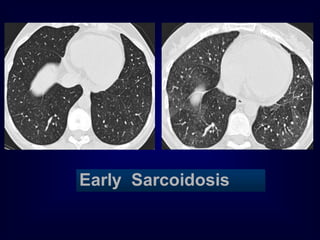

Early Sarcoidosis